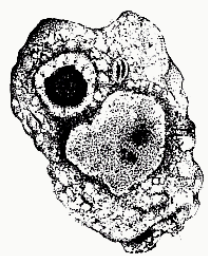

Iodamoeba butschlii (troph)

Iodamoeba butschlii (troph)